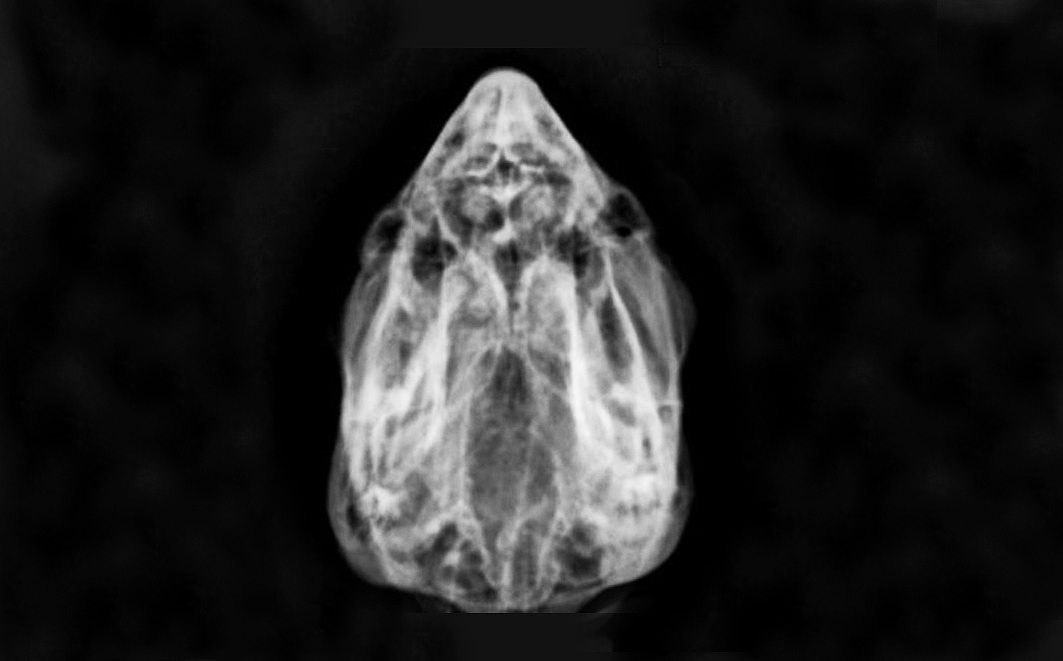

Um maracanã-nobre (Diopsittaca nobilis), sexo indeterminado, pesando 168 g (gramas), jovem, foi atendida em uma clínica particular, após ter sido encontrada por munícipe em via pública abaixo de um grande vitral em ponto comercial da cidade. Ao exame físico a ave apresentava-se com sinais de incoordenação motora, olhos fechados, lateralização de cabeça, hematoma em face lateral esquerda e sangramento pelas narinas (Figuras 2 e 3), hipotermia leve 39,2 °C graus, levando a suspeitas de trauma crânio encefálico. A ave apresentava sinais de Glasgow moderado sugestivo em 10.

Também foi realizado como exame complementar a radiografia de crânio para investigar lesões intra e extracranianas (Figuras 6 e 7). O mesmo apontou edema em região de olho direito (Figura 8). Nessa radiografia de crânio não se evidenciaram lesões extracranianas. Após 24 horas a ave demonstrou melhora clínica do quadro neurológico conseguindo deambular, mímica de vocalização e parcial abertura dos olhos (Figuras 9 e 10).